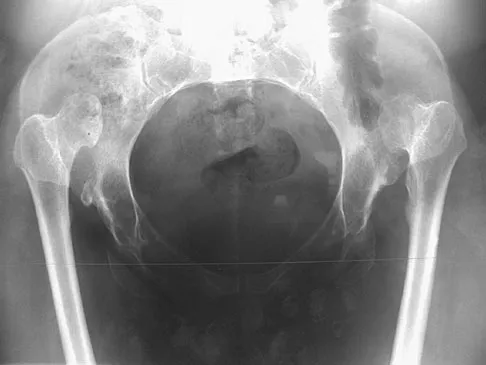

Question 19

Based on the radiograph shown in Figure 4, the innervation of what muscle is most at risk with total hip arthroplasty?

Explanation